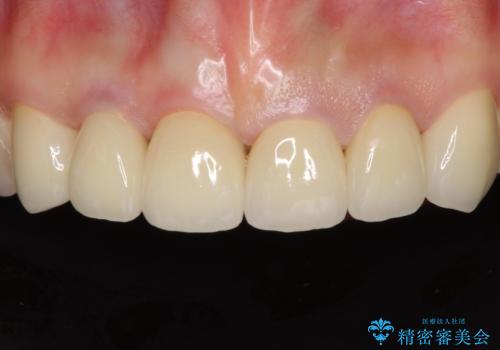

セラミッククラウン装着後は、とても自然な口元に仕上がりました。